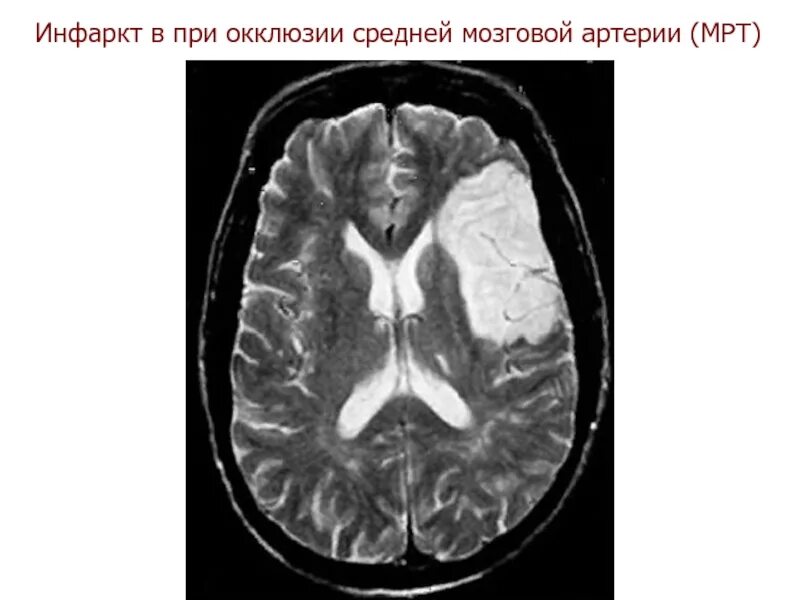

Онмк в бассейне сма